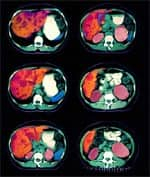

Recent studies suggest that some Asians—who demonstrate genetic polymorphisms, or variability in the genes that code for the enzymes alcohol dehydrogenase and aldehyde dehydrogenase—are at elevated risk of developing alcohol- related liver disease, as are African-Americans of either sex.38,39 In fact, African-Americans have been dying of liver cirrhosis at a greater rate than whites of comparable age for the last 40 years.40 However, neither men nor women enjoy any relative advantages when it comes to protecting against the toxic effects of the powerful 1-hydroxy-ethyl radical. Because alcohol has substantial caloric value (7.1 calories per gram), it may displace ordinary nutrients in the diet, including antioxidants such as vitamin C, thereby causing primary malnutrition.23 Secondary malnutrition can occur later in the course of chronic alcohol use, when food is no longer properly digested and absorbed by the gastrointestinal tract.30,41-43 Long-term alcohol abuse often leads to a condition known as cirrhosis, which is responsible for the high rate of mortality among heavy drinkers. While liver disease was long thought to be caused by malnutrition, scientists eventually demonstrated that alcohol causes liver cirrhosis even in the absence of nutritional deficiencies. Liver cirrhosis was the twelfth leading cause of death in the US in 2000.35,44 The correlation between alcohol intake and cirrhosis is confirmed in epidemiological data gathered in the last century. For example, Canadian scientists recently analyzed alcohol consumption and cirrhosis incidence in the US before, during, and after Prohibition. The data provide striking evidence of the close correlation between drinking and incidence of the disease. As alcohol consumption plummeted during the Prohibition era, cirrhosis closely followed suit. With the repeal of Prohibition, drinking resumed with gusto, as did diagnoses of fatal liver cirrhosis. The nefarious cause-and-effect relationship between alcohol consumption and deadly cirrhosis continues to this day.35 | ||||||

Alcohol and the LiverDuring first-pass metabolism of alcohol, the coenzyme nicotinamide adenine dinucleotide (NAD) is converted to its reduced form, NADH. NAD and NADH are compounds involved in the synthesis of the energy molecule adenosine triphosphate (ATP) within the mitochondria. Production of excess NADH upsets the delicate reduction/oxidation, or redox, balance in liver cells. Excess alcohol ingestion promotes fatty acid synthesis, causing a rise in liver fatty acid content. This saturates the liver with lipids, causing “fatty liver,” or steatosis, a first step on the path to more serious liver disease. Elevation of blood lipids, including high-density lipoprotein (HDL), may also occur.23 In recent years, the mild increase in HDL induced by alcohol has been touted as playing a beneficial role in the reduction of cardiovascular disease and incidence of stroke.23 But alcohol’s other effects are less benign. The acetaldehyde produced during alcohol metabolism is a mutagenic agent, capable of producing harmful genetic mutations that may trigger various cancers.45-47 Some of alcohol’s worst effects, however, are caused by the free radicals produced as a result of its metabolism. These rogue molecules steal hydrogen ions from fatty acids in the cell membranes, triggering a chain reaction that damages or destroys cell membranes, a process referred to as lipid peroxidation.48 Metabolism of alcohol provokes a striking increase in the activity of cytochrome P450 liver enzymes, especially a subset enzyme known as 2E1. Studies show that 2E1 liver enzymes are four to 10 times higher in people who have recently consumed alcohol than in non-drinking controls. This liver enzyme converts various compounds to highly toxic metabolites. One consequence of drinking, therefore, is the production of toxic metabolites that would otherwise not occur. For example, many pesticides are normally converted to non-carcinogenic compounds in the livers of non-drinkers. But among alcohol drinkers, they are converted to carcinogens—compounds known to have cancer-promoting properties.47